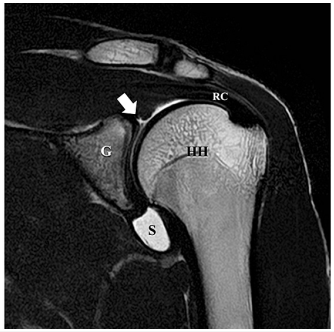

MRI 촬영 결과 Type 2 SLAP 병변이 확인되었지만 재활에도 통증이 개선되지 않아 다른 관점으로 접근이 필요했습니다. SLAP 병변은 무증상인 경우도 많아서 지금 당장 아픈 원인이 아닌 경우가 있는데요. 다른 부분들 먼저 치료하고도 해결이 안 될 때 수술을 고려합니다.  DOI: 10.7759/cureus.60157 여기서 주목한 점은 해당 선수가 SLAP 병변 외에도 어깨 관절의 '가동 범위 제한'이 심했다는 겁니다. 우리가 어깨 관절을 검사할 때 쓰는 두 가지 테스트에서 양성으로 나왔는데요. 1. 결합 외전 검사(CAT, Combined Abduction Test): 견갑골을 고정한 뒤 팔을 위로 올려(Flexion) 가동 범위가 줄어드는지 보는 검사 2. 수평 굴곡 검사(HFT, Horizontal Flexion Test): 어깨를 몸통 쪽으로 수평하게 모을 때 가동 범위가 줄어드는지 보는 검사

DOI: 10.7759/cureus.60157 여기서 주목한 점은 해당 선수가 SLAP 병변 외에도 어깨 관절의 '가동 범위 제한'이 심했다는 겁니다. 우리가 어깨 관절을 검사할 때 쓰는 두 가지 테스트에서 양성으로 나왔는데요. 1. 결합 외전 검사(CAT, Combined Abduction Test): 견갑골을 고정한 뒤 팔을 위로 올려(Flexion) 가동 범위가 줄어드는지 보는 검사 2. 수평 굴곡 검사(HFT, Horizontal Flexion Test): 어깨를 몸통 쪽으로 수평하게 모을 때 가동 범위가 줄어드는지 보는 검사  B,D 그림처럼 해당 검사에서 양성이라는 건, 어깨 관절의 아랫쪽과 뒷쪽이 꽉 조여져 있다는 것을 의미합니다. 정상적으로 팔을 들 때에는 어깨뼈와 팔뼈가 미끄러지듯이 움직여야 하는데, 관절이 꽉 조여 있으면이 중심축이 자꾸 틀어지게 됩니다. 이렇게 되면 팔을 올릴 때마다 SLAP 병변 위치에더 큰 압력이 가해지고,증상이 계속해서 악화되었던 것이죠. > 신경의 유착이 > > 어깨를 꽉 잡고 있다! 그렇다면 어깨 움직임을 제한하는 ‘꽉 조이는 느낌’은 어디에서 오는 걸까요? 연구진은 CAT와 HFT 검사 시 가장 심하게 늘어나는 신경을 주목했습니다. ◆ CAT (어깨 올림) 검사 시: 어깨 관절 아래쪽에 위치한 흉배신경 (Thoracodorsal Nerve, TDN)이 가장 늘어나고요. 광배근(Latissimus Dorsi) 등의 중요한 근육을 지배합니다. ◆ HFT (수평 모으기) 검사 시: 어깨 관절 뒤쪽에 위치한 액와신경 (Axillary Nerve, AxN)이 가장 늘어나고, 소원근(Teres Minor)과 같은 근육을 지배합니다. 이 사례에서는 이 두가지 신경 주변 조직이염증으로 인해 유착되면서어깨의 가동 범위를 제한하고, 결과적으로 SLAP 병변의 통증을 유발했다고 가설을 세웠습니다. 즉, 구조적인 문제가 아니라 신경 포착 증후군이 통증의 원인일 수 있다는 새로운 관점이죠. > 관절경 수술이 아닌 > > 비수술 치료 그래서 선택한 치료법이 바로 ‘하이드로다이섹션(Nerve Hydrodissection)’, 즉 신경 박리술입니다.